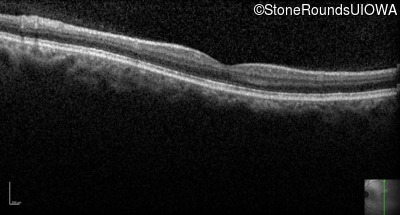

Optical Coherence Tomography - Left - 20/160 -1

Exemplar / OCT Stack